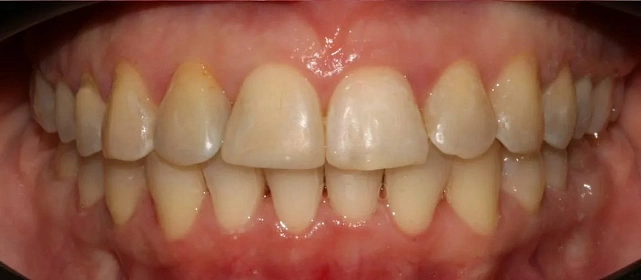

Проблема: В клинику обратилась пациентка — беспокоили неровные зубы и неправильное смыкание. Зубные ряды сходились некорректно, зубы стояли со смещением, что влияло и на внешний вид, и на распределение нагрузки при жевании.

Решение: Поставили элайнеры 3D Smile на обе челюсти. Лечение заняло 4 года и потребовало нескольких последовательных этапов коррекции. Капы менялись каждые 1–2 недели, на контрольных визитах отслеживали прогресс и выдавали новые наборы. Зубы встали в правильное положение, смыкание нормализовалось. Зафиксировали ретейнеры на обе челюсти, изготовили ретенционные капы. Пациентка прошла онлайн-консультацию с ортопедом для оценки дальнейших шагов.

Зубы выровнены, смыкание нормализовано. Установлены несъёмные ретейнеры на обе челюсти, изготовлены ретенционные капы. Пациентка предварительно проконсультирована ортопедом онлайн.